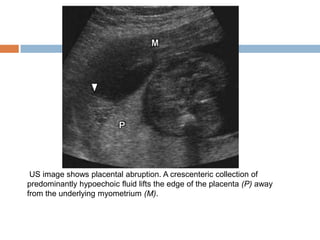

Placental Abruption

   Placental abruption represents premature

separation of the placenta from the uterine wall

   US is frequently performed to confirm the

presence of abruption and assess the extent of

subchorionic or retroplacental hematoma . The

presence of blood in large enough volumes to be

visible sonographically indicates retained

hemorrhage that may remain symptomatic.

   False-negative results can occur when blood

dissects out from beneath the placenta and drains

through the cervix.

US image shows placental abruption. A crescenteric collection of

predominantly hypoechoic fluid lifts the edge of the placenta (P) away

from the underlying myometrium (M).

Placental Abruption  Placental abruption represents premature separation of the placenta from the uterine wall  US is frequently performed to confirm the presence of abruption and assess the extent of subchorionic or retroplacental hematoma . The presence of blood in large enough volumes to be visible sonographically indicates retained hemorrhage that may remain symptomatic.  False-negative results can occur when blood dissects out from beneath the placenta and drains through the cervix.

US image showsplacental abruption. A crescenteric collection of predominantly hypoechoic fluid lifts the edge of the placenta (P) away from the underlying myometrium (M).